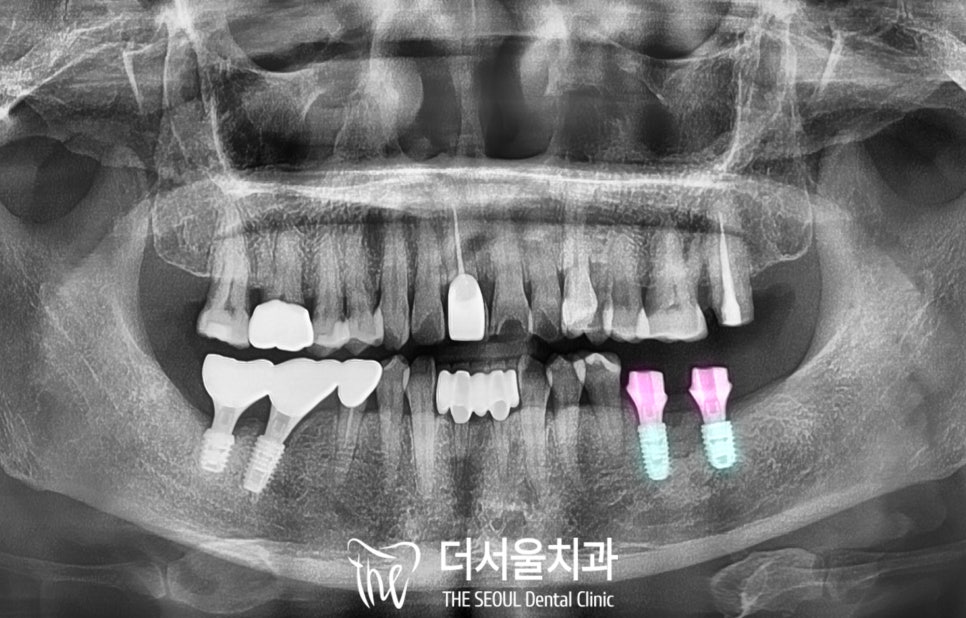

2. 파노라마 엑스레이 분석

태평역치과 에서

파노라마 엑스레이를 찍어보니

치아를 감싸고 있는

치조골에 염증이 생겨

녹아있었습니다.

이 케이스에서도 뿌리 끝까지

진행된 치주 질환으로

발치를 판정했습니다.

4. 픽스처 식립

디지털 임플란트를 계획한 대로

식립을 마친 모습을 보겠습니다.

보이는 것처럼

하치조 신경과 거리를 유지하며

예측했던 곳으로

두 개의 픽스처를 심었습니다.

또한 부족한 곳은 일부

추가 골이식을 통해 보강해 드렸습니다.